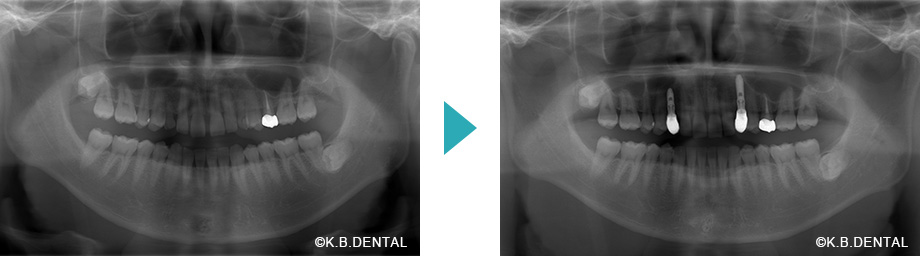

すきっ歯・乳犬歯の晩期残存の症例

| 主訴 | 上顎前歯のすきっ歯を治したい。乳犬歯を抜いてインプラントにしたい。 |

| 診断名 | 上顎中切歯の正中離開および乳犬歯の晩期残存 |

| 初診時年齢/性別 | 32歳男性 |

| 装置 | マウスピース矯正(インビザラインGo)+矯正によるスペースメイキングした乳犬歯部分への抜歯インプラント即時埋入 |

| 抜歯/非抜歯 | 非抜歯(乳犬歯は抜歯→インプラントへ置換) |

| 治療期間 | 約1年半 |

| 費用 | 約160万円(税別) |